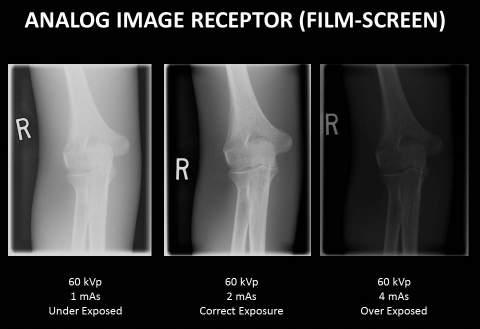

The epiphyses are the parts of bones that increase in size and appearance as a child grows, as is shown on the growth comparison radiographs (Figs. 16-12 to 16-15). These four knee radiographs show the changes in size and shape of the epiphyses of the distal femur and proximal tibia and fibula from age 3 years to age 12 years. At age 3 years, the epiphysis of the fibula is not yet visible, but by 12 years of age, it becomes obvious (see arrows). The size and shape of the larger epiphysis of the proximal tibia and distal femur also change dramatically from age 3 to age 12, as is evident on these knee radiographs.